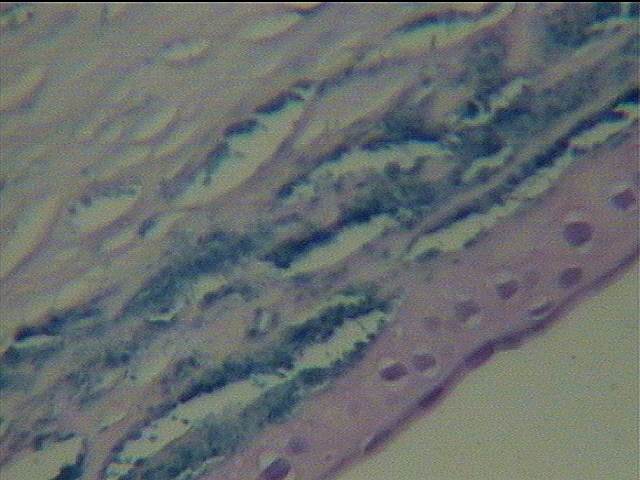

組織病理學變化:角膜上皮厚薄不均。前彈力膜部分破壞、斷裂或分裂成數層。實質板層擺列較疏松。在實質纖維之間有甚多大小不等的柳葉狀或梭形空隙。部分角膜實質細胞胞質豐富而核固縮。后彈力膜普遍增厚呈板層狀,或呈滴狀突伸向前房。內皮細胞數目減少,部分壞死,胞膜破裂,胞核固縮。病變物質分布在上皮下前彈力膜前后的空泡細胞、角膜實質細胞及內皮細胞的胞質內外及實質層空隙內。此種物質在HE染色片中呈嗜堿性淡藍灰色,PAS染色僅淡紫紅色,剛果紅及Masson三色不著色。唯有膠性鐵染色呈非常醒目的鮮藍色。此種染色是病理鑒別斑塊狀營養不良的最重要方法。(圖1-1、1-2)

圖1-1膠體鐵染色×100

圖1-2膠體鐵染色×400